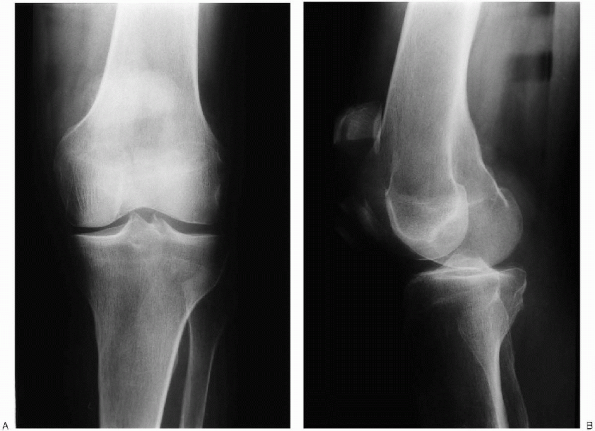

![]() |

FIGURE 29-2. Anteroposterior (A) and lateral (B) radiographs show a displaced patella fracture.